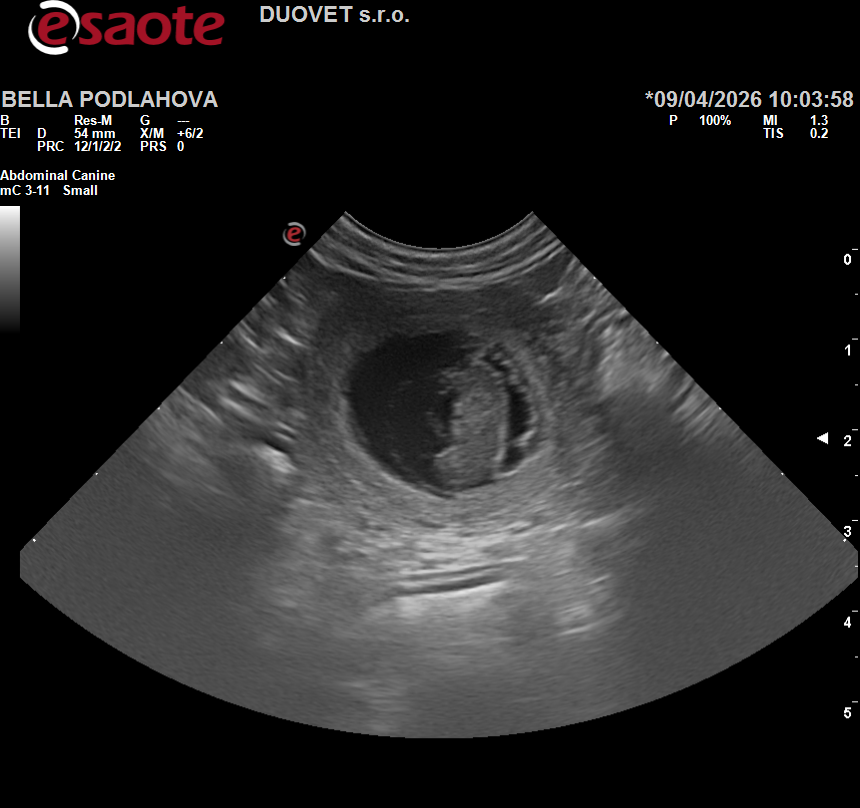

Chovatelská stanice „od Rebenky“ oznamuje radostnou zprávu, že u naší fenky „Belly“ byla potvrzena březost a štěňátka z vrhu „D“ se narodí v druhé polovině května 2026.